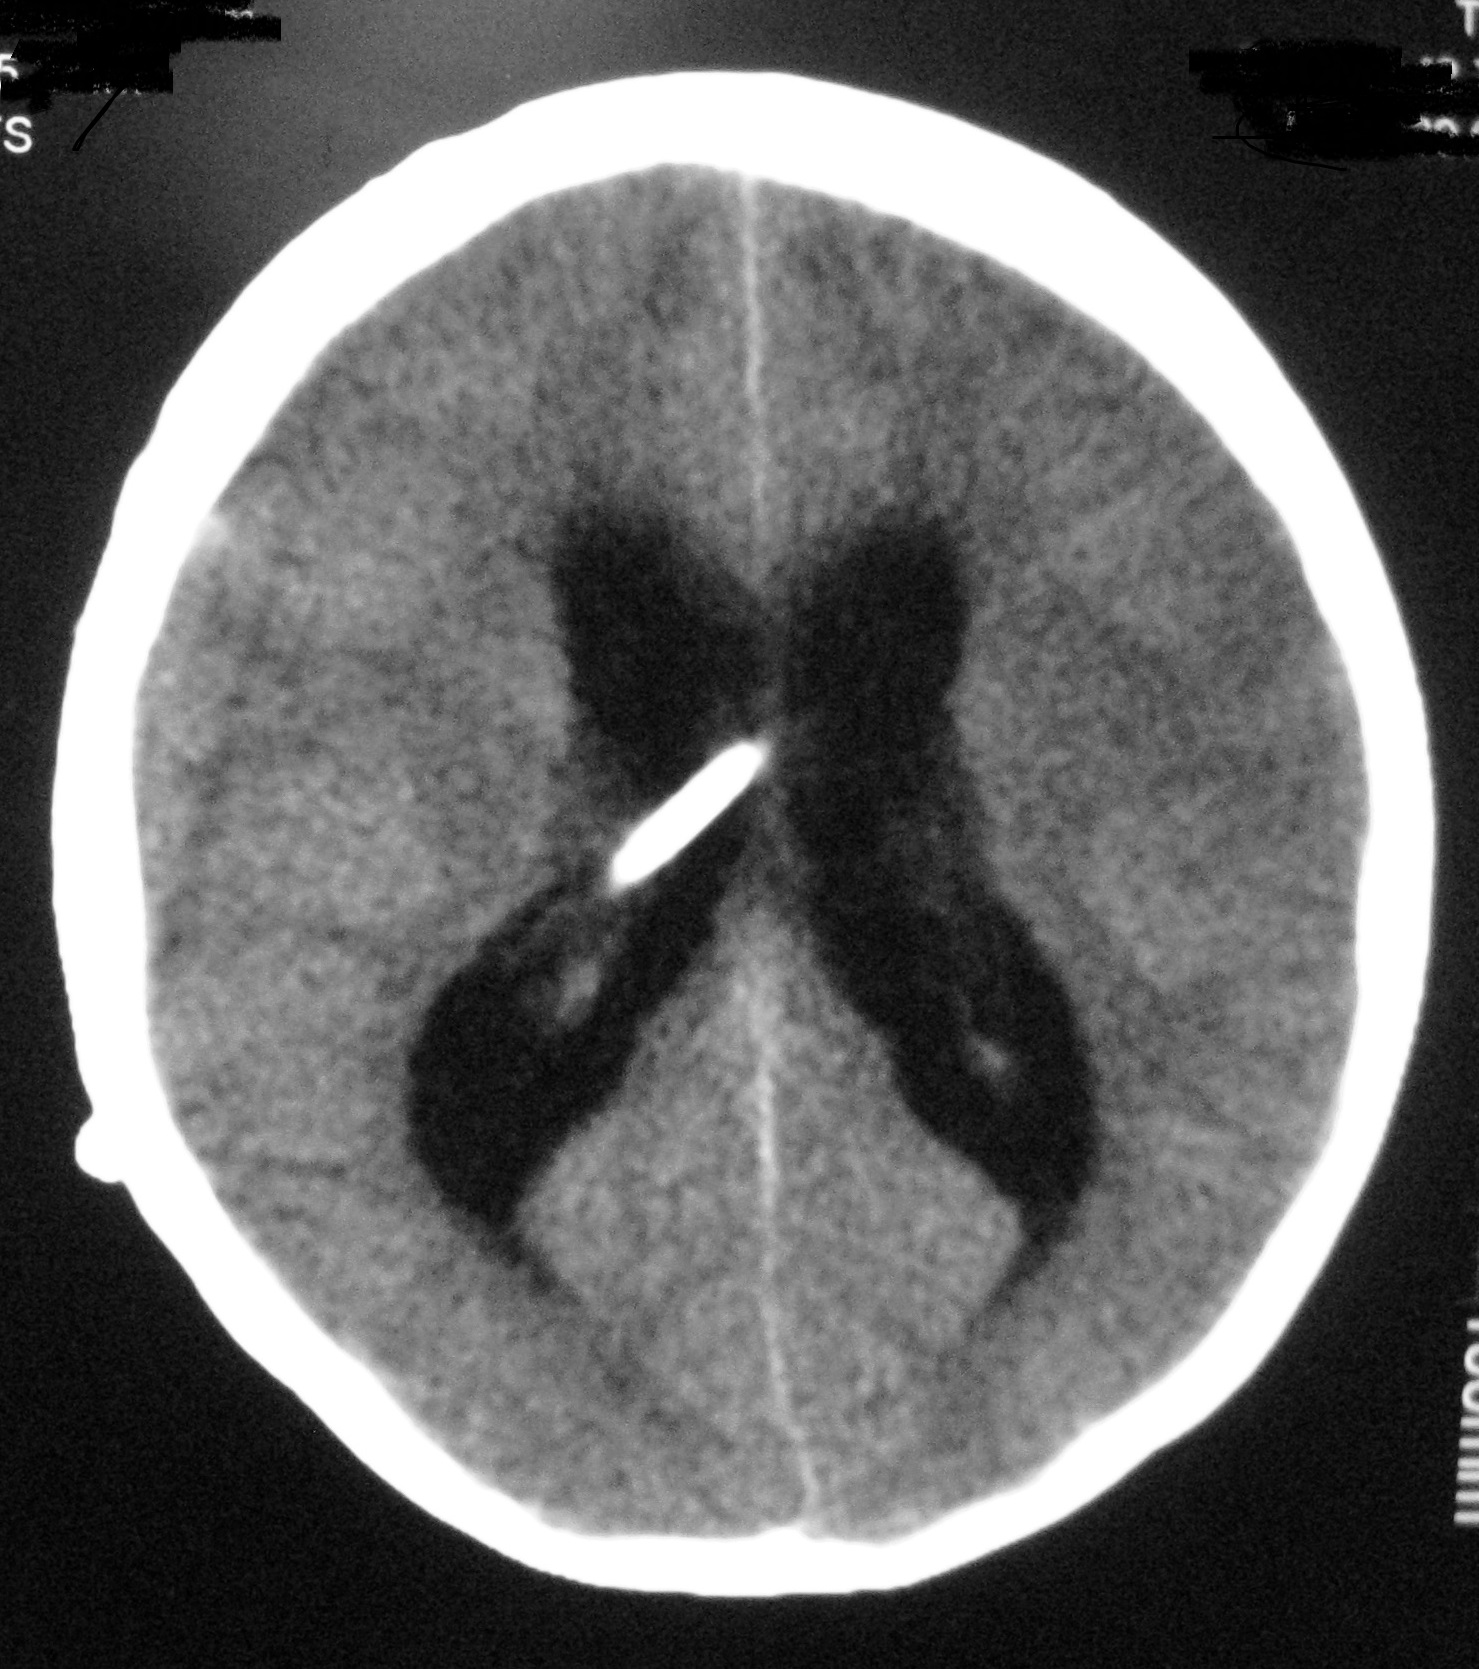

The signs and symptoms of shunt dysfunction are related to high intracranial pressure most commonly including headache, nausea, vomiting, bulge fontanel, irritability, sunset eye. Increased ventricular diameter in comparison to prior studies, increased temporal horns width, sulcus effacement and rounding of 3rd ventricle are common findings in neuroimaging studies during shunt malfunction (Figure 1). However, stable ventricular dimensions on serial imaging studies (Figure 2) may wrongly be interpreted as normal shunt function [4].

Figure 2: A. Slit like ventricle after 9 months of shunting in an infant with congenital hydrocephalus; the child was stable without any symptoms. B. One year later he was admitted with persistent vomiting and ptosis. The brain CT shows no obvious change in the size of ventricle. His symptoms were recovered after shunt revision due to proximal catheter obstruction.